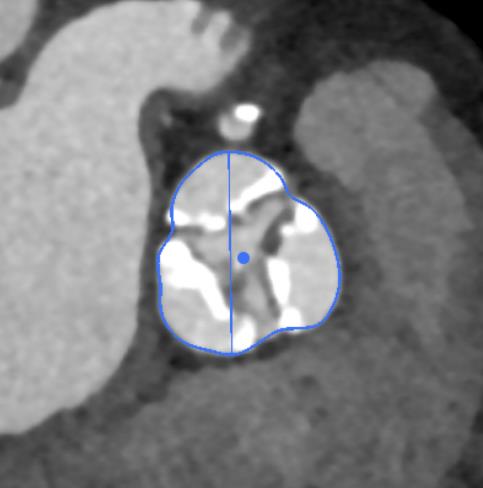

(图1,患者术前3D-CT评估)

(图2,主动脉窦部CT平面,可见主动脉瓣为三叶瓣、瓣叶增厚并严重钙化)

经过充分细致地准备,多学科积极协作,在张希全主任指导下,心血管外科谷兴华主任医师、急诊心内科李传保主任医师、心血管外科孙厚荣副主任医师及团队成员在绿帽社复合手术室实施手术。根据患者的病情特点,术中做好各种应急预案,备好体外循环,维持血流动力学平稳。根据术前CT分析和术中主动脉根部造影情况(图1、图2、图3),选择最佳投照体位。先选用22mm球囊,临时起搏180次/分,扩张重度狭窄的主动脉瓣(图4)。再选用24mm的介入主动脉瓣膜,造影、定位、临时起搏、顺序释放介入瓣膜,造影及心脏超声检查示:人工瓣膜位置形态满意,瓣膜启闭功能正常,主动脉瓣无瓣周分流,跨瓣压差降至8mmHg(图5、图6)。术后1小时,麻醉清醒,术后8小时顺利脱机拔管,术后第2天转入普通病房,病情稳定,治愈出院。